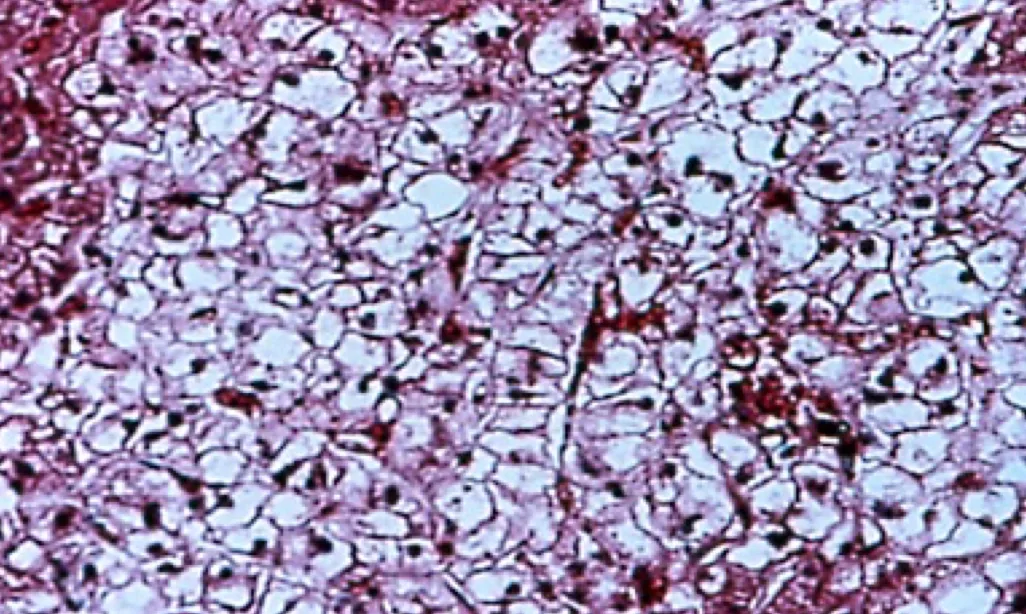

The liver of a dog with cirrhosis due to chronic hepatotoxicity from phenobarbital is shown in Figure 2. Typical findings include increased total ALP usually less than 5 times upper limit of normal, with ALT usually less than 2 times upper limit of normal. GGT, AST, total serum bile acids should be within the normal range.11,12 Ultrasonography yields normal findings, and most dogs do not have hepatomegaly. Biopsy shows diffuse cytoplasmic granularity due to proliferation of smooth endoplasmic reticulum.

Cirrhotic liver in a dog secondary to chronic hepatotoxicity from phenobarbital

Signs of possible hepatotoxicity include abnormal hepatic function tests. ALT, GGT or AST elevations more than 2 times the upper limit of normal. Hepatic biopsy shows chronic inflammatory/fibrotic disease.13 Treatment involves weaning from phenobarbital and onto alternative antiseizure medications, such as potassium bromide; controlling the complications of hepatic failure; and initiating hepatoprotective therapy with ursodeoxycholate and/or S-adenosylmethionine.